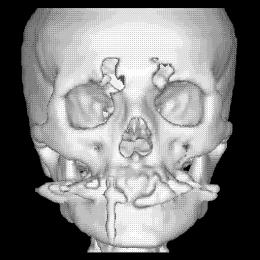

La figura 1‑9 mostra un esempio di surface rendering. Si noti come grazie all’ombreggiatura si avverte la sensazione di tridimensionalità.

Figura 19 Ricostruzione 3D in surface rendering